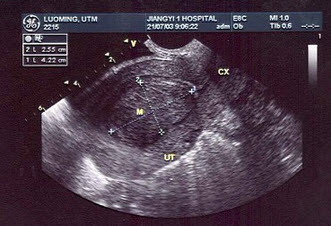

女性,36岁,行常规超声妇科体检。声像图表现如图。血HCG为2258μg/ml。最可能的诊断是()

A.绒癌

B.子宫腺肌瘤

C.早期妊娠

D.子宫肌瘤

E.良性葡萄胎